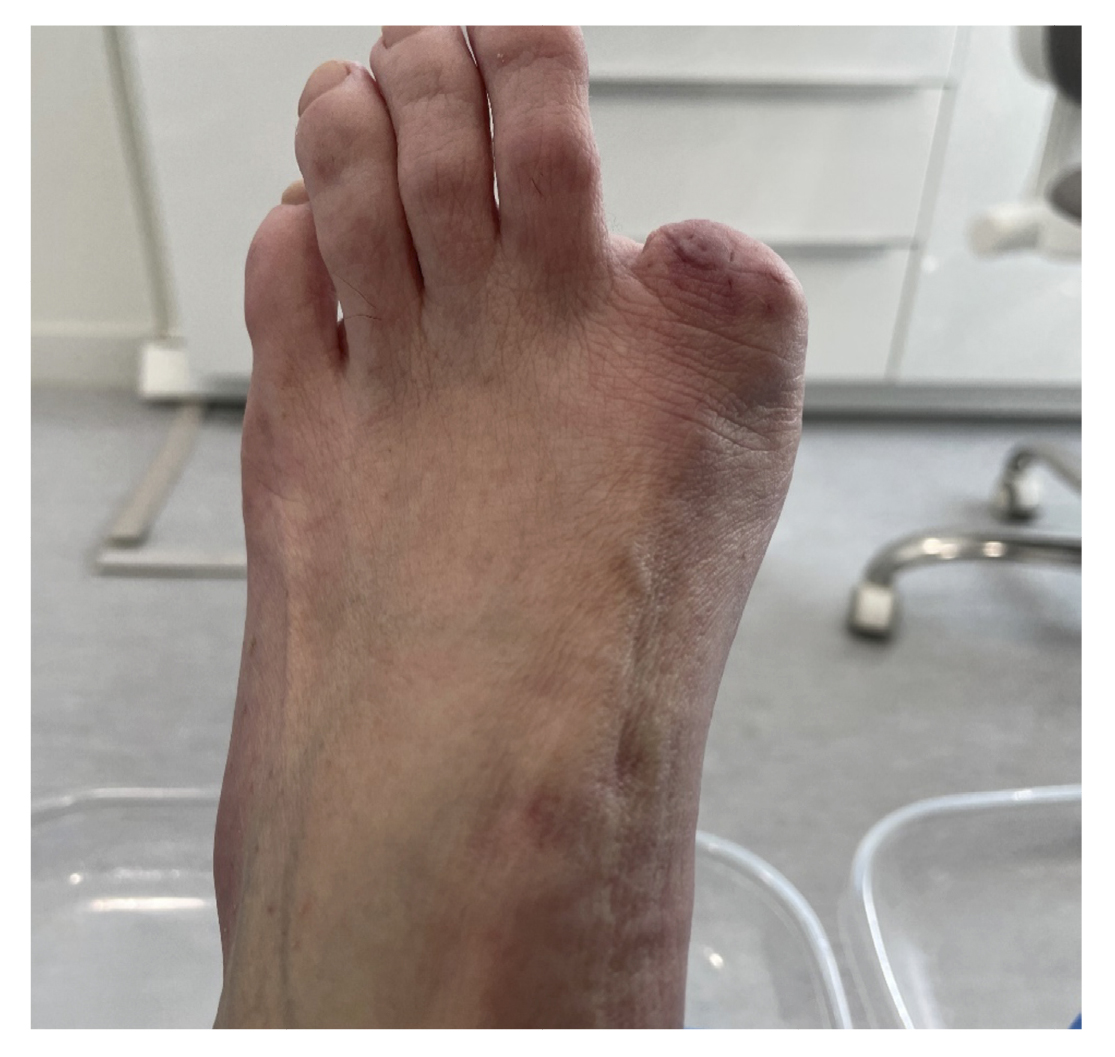

The patient reported a 7-month history onychocryptosis (September 2022) on the medial border of the first toe of the left foot, with presence of ungual granulation tissue on said border, causing her pain and digital inflammation (Figure 1). The patient received treatment from her podiatrist consisting of chiropody and canal cleaning, and then daily dressings with mupirocin were prescribed for the lesion. The lesion showed poor progression in the following days with increased pain and tenderness to the touch. Treatment was modified to amoxicilin/clavulanic acid 875/125 mg, 1/8 hours along with the use of oral analgesics (Figure 2). The patient continued with poor symptomatic evolution and attended her health center where an X-ray was performed, ruling out the presence of deep infection (osteomyelitis).

Figure 1. Initial process of onicochryptosis and reactive granuloma.

5 days postoperatively, the patient’s first dressing change was performed, which showed a good appearance and no local infection. The patient was explained the result of pathology and referred to the oncology service of her hospital, and from there to the dermatology and plastic surgery service where digital amputation was performed (Figure 10). Subsequent follow-up was conducted by the Oncology service for the next 6 months. After different tests, it was determined that no other treatment was needed. Figure 11 shows the timeline of the clinical case.